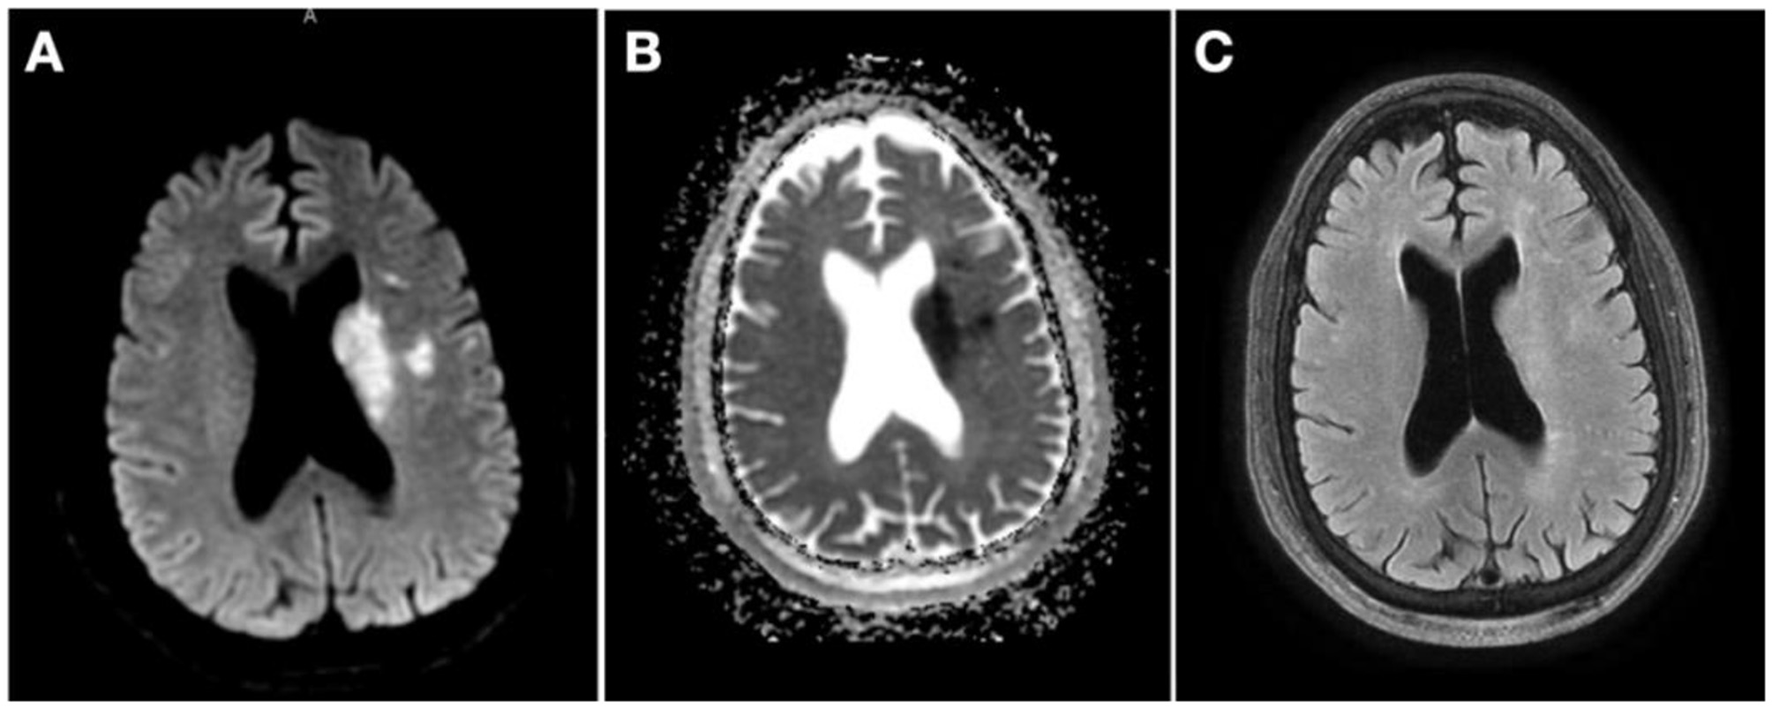

The patient was admitted for further stroke management and remained clinically stable, with residual deficits of mild right upper extremity weakness and mild expressive aphasia. Brain magnetic resonance imaging (MRI) obtained ~12 h after presentation confirmed small acute infarcts on the left subcortical frontal lobe and basal ganglia (Figures 3A–C). The patient was started on dual antiplatelet therapy with aspirin and clopidogrel 24 h after IVT.

Figure 3. Magnetic resonance imaging (MRI) 12 h from presentation. (A) MRI diffusion-weighted imaging showing multiple hyperintense foci on left basal ganglia and left subcortical frontal lobe; (B) MRI apparent diffusion coefficient with corresponding hypointensity in the same territories; (C) MRI fluid-attenuated inversion recovery showing mild hyperintensity in the same territories.

Four weeks after the first procedure, the patient was readmitted for the second stage of stenting. There was interval clinical improvement with only residual minimal aphasia. The patient finally underwent left ICA stenting without complications (Figure 5). On a 90-day follow-up assessment, the patient continued to improve to full resolution of previous weakness and speech impairment and was able to resume their previous activities.

Figure 5. Computerized tomography perfusion (CTP) and digital subtraction angiography 1 month after contralateral stenting. (A) CTP 28 days after right internal carotid artery stenting showing no core or penumbra on left middle cerebral artery territory; (B) Left common carotid artery (CCA) injection, neck lateral view pre-stenting; (C) Left CCA injection, neck lateral view post-stenting.